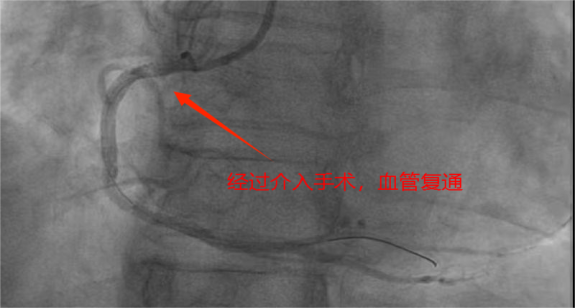

医院导管室内,早已严阵以待的介入团队迅速投入到抢救工作中。穿刺、血管造影、精准找到堵塞血管、球囊扩张…… 一系列复杂的操作,在团队成员的默契配合下紧张、有序地进行;每一个步骤都精准高效,每一秒都在与死神赛跑。最终,从患者进入医院大门到堵塞的血管被成功开通,仅仅用时 20 分钟!这一惊人的数字,远远低于国际标准的 90 分钟,不仅刷新了医院胸痛中心的速度纪录,最大程度减少心肌缺血时间。

术后,患者的生命体征很快趋于平稳,心率、血压恢复正常,安全转入 CCU(心脏监护病房)进行后续治疗,在医护人员的精心照料下,康复出院。